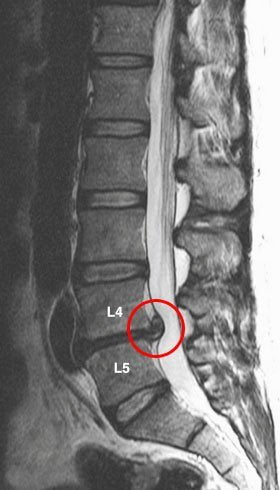

Удаление межпозвоночной грыжи: все о хирургическом лечении

Операция по удалению межпозвоночной грыжи шейного, поясничного, грудного отдела позвоночника выполняется различными способами. Чаще всего используются дискэктомия, ламинэктомия, нуклеопластика. Но хирургическое вмешательство действительно необходимо примерно в 10-15% случаев грыжи межпозвонкового диска. Оно показано пациентам с уже возникшими тяжелыми осложнениями, имеющими тенденцию к прогрессированию.